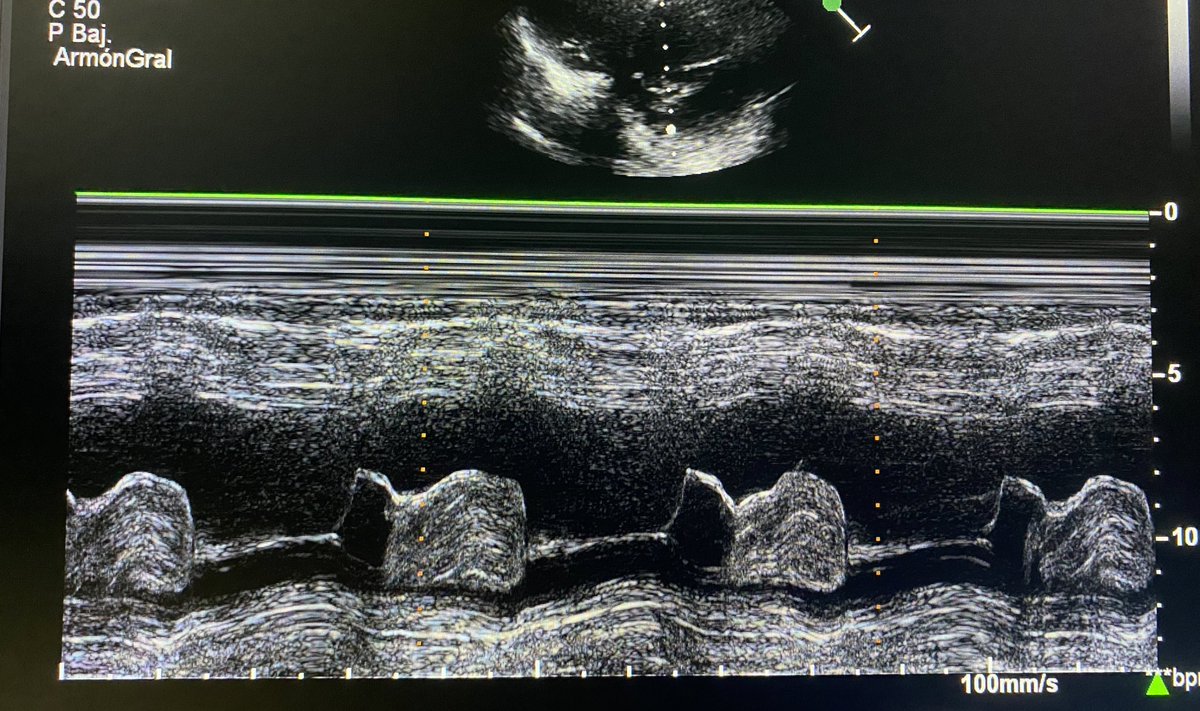

💡¿Qué es? y ¿Cómo identificar la cardiotoxicidad?